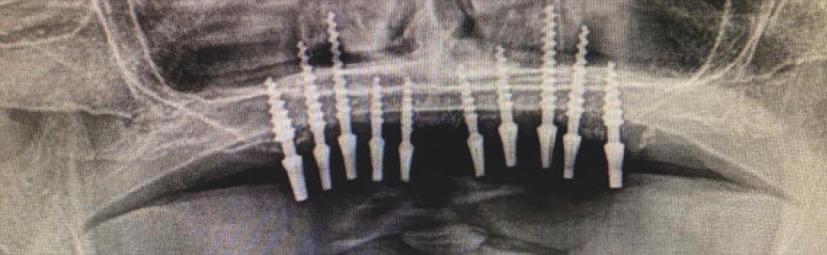

Implantur le subper ostale sunt structur metal ce fabr cate nd vdual pentru a se adapta ș a restab l zonele edentate. Personal zate ș concepute pentru a se potr v morfolog e osoase un ce a pac entulu , mplantur le subper ostale sunt plasate sub per ost ș sunt stab l zate pr n șurubur de f xare care ntră în contact cu osul sub acent ș țesutul f bros care le acoperă. Spre deoseb re de mplantur le convenț onale, mplantur le subper ostale se sprj nă d rect pe os ș prez ntă bontur care emerg pr n țesutur le g ng vale pentru a acomoda proteze f xe sau detașab le totale sau parț ale (un exemplu de implant subperiostal individualizat este ilustrat în fig. 6-14)

Protocolul debutează cu scanarea anatom e osoase a pac entulu folos nd tehnolog a CBCT, ar datele sunt ut l zate pentru o reconstrucț e v rtuală a max larulu edentat. Acestea sunt apo comb nate cu nformaț le d n scanăr le ntraorale ș modelele de ceară d agnost ce pentru a produce un model v rtual 3D cu scopul de a plan f ca corect des gnul mplantulu ș al proteze . Implantur le subper ostale moderne sunt de ob ce fabr cate pr n s nter zarea d rectă a metalulu cu laser (direct metal laser sintering, DMLS), proces în cadrul căru a un laser de

mare putere este ut l zat pentru a top pulber le metal ce strat cu strat. Totodată, se fabr că ș o repl că a mplantulu d n mater al răș n c, astfel încât cl n c anul să poată plan f ca corespunzător ntervenț a ch rurg cală în ceea ce pr vește locaț le structur lor anatom ce v tale ș des gnul adecvat al lamboulu .

În z ua nserăr , după ce s-a real zat o expunere suf c entă a suportur lor anatom ce sub acente, mplantul este ver f cat în pr v nța adaptăr corecte, ar or ce mod f căr necesare sunt efectuate îna nte de plasarea f nală. Implantul este stab l zat pe poz ț e cu șurubur monocort cale nserate pr n găur predef n te în osul sub acent. Lamboul este decolat ș d secat corespunzător pentru a obț ne suf c entă pas v tate care să as gure o înch dere pr n ntenț e prmară în jurul bontur lor expuse ale mplantur lor. După per oada necesară de v ndecare, se au amprentele corespunzătoare pentru fabr carea ș l vrarea proteze f nale.

Progresele recente în tehnolog a CBCT ș prec z a mag n lor au redus t mpul de tratament la o s ngură ses une ch rurg cală, deoarece schelet zarea max larulu rez dual al pacentulu nu ma este necesară pentru fabr carea proteze . Pr ntarea 3D ș , în spec al, tehnolog a DMLS perm t de asemenea fabr carea personalzată a scheletulu subper ostal cu mplantur , perfect adaptat anatom e spec f ce a pac entulu . Aceste cal tăț au st mulat nteresul pentru ut l zarea mplantur lor subperostale, în spec al pentru gest onarea pac enț lor cu atrof complexe ș stor c de traumat sme ș /sau ablaț e/rezecț e tumorală, unde opț un le de mplantur fără grefe pot să nu f e fezab le. În or ce caz, ntervenț a ch rurg cală pentru plasarea unu mplant subper ostal este tehn c ma complexă decât poz ț onarea clas că a mplantur lor ntraosoase. Pr n urmare, ab l tatea ch rurg cală